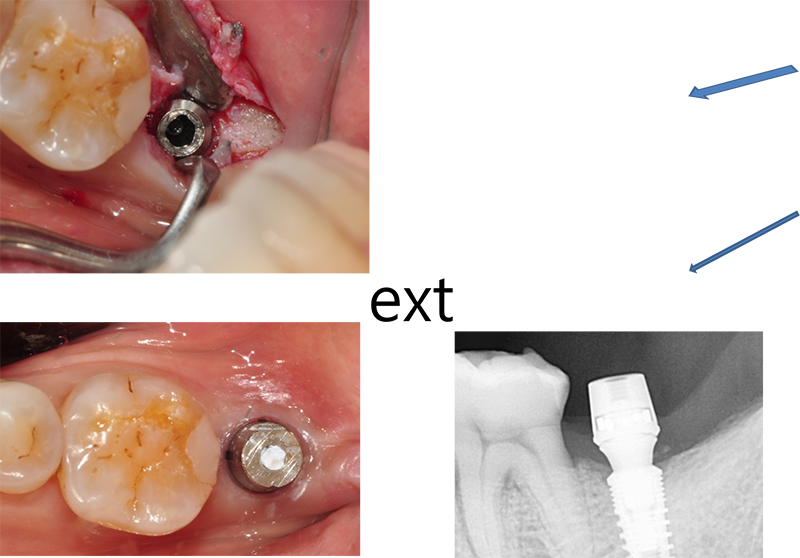

37번 4.3 직경의 원플란트

제거하다가 흠집이 날 것 같아서 포기하고

다음에 약속 잡았는데 환자도 저도 미루다가 이 지경됨.

파노라마 상

결국 픽스쳐 제거

아마도 교합에 문제가 있었던 듯

37번 abutment 파절, 뒤쪽에 8번이 보이고, fixture 직경이 5.0, 조금 흠집이 나도 된다는 생각으로 제거수술을

했다.

3번에

나눠서 겨우 제거한 경우